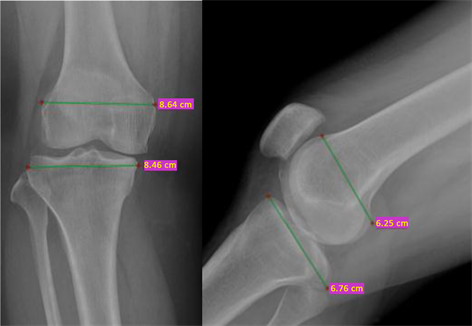

For male, average weight was 63 ± 13 kg, height was 168 ± 10 cm and average BMI was 22 ± 5.17 kg/m2. For female average weight was 65 ± 12 kg, height was 167 ± 10 cm and average BMI was 23 ± 5.3 kg/m2. Average FML was 62.6 ± 7.45 mm in male and 59.1 ± 5.79 mm in female participants. Average FAP was 70.6 ± 1.22 mm in male and 66.9 ± 3.93 mm in female. Average TML in male was 85.6 ± 1.27 mm and 79.1 ± 0.8 was in female. Average TAP was 60.1 ± 4.87 mm in male and 55.7 ± 4.96 in female. Average PAP was 22.5 ± 2.83 mm in male and 23.8 ± 2.43 mm in female. Average PML was 50.2 ± 1.45 in male and 46.8 ± 4.09 mm in female (Figure 3, Figure 4).

Figure 3. Anterior-posterior and lateral image of knee joint X-ray (FML-86.4 mm, TML-84.6 mm, FAP-62.5 mm, TAP-67.6 mm).